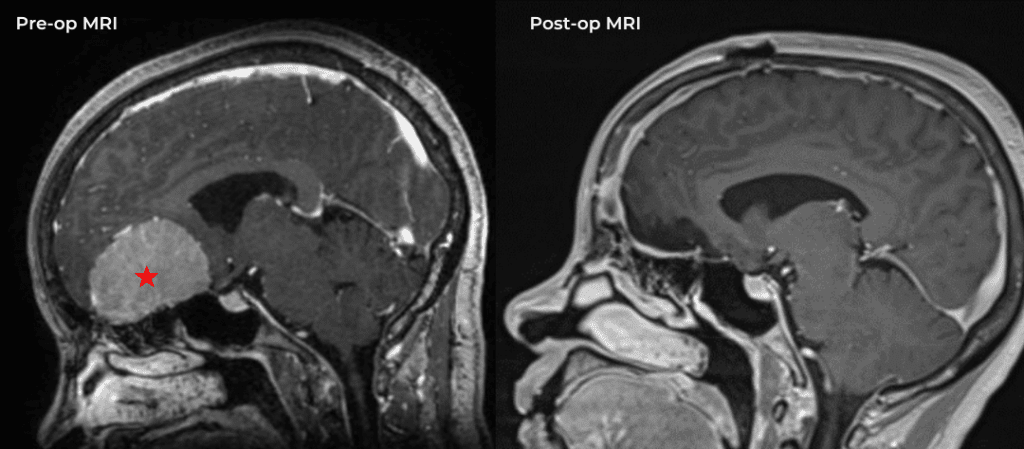

Brain:

Cerebellar Hemangioblastoma

Author: Michael Brisman M.D., F.A.C.S., Read More!